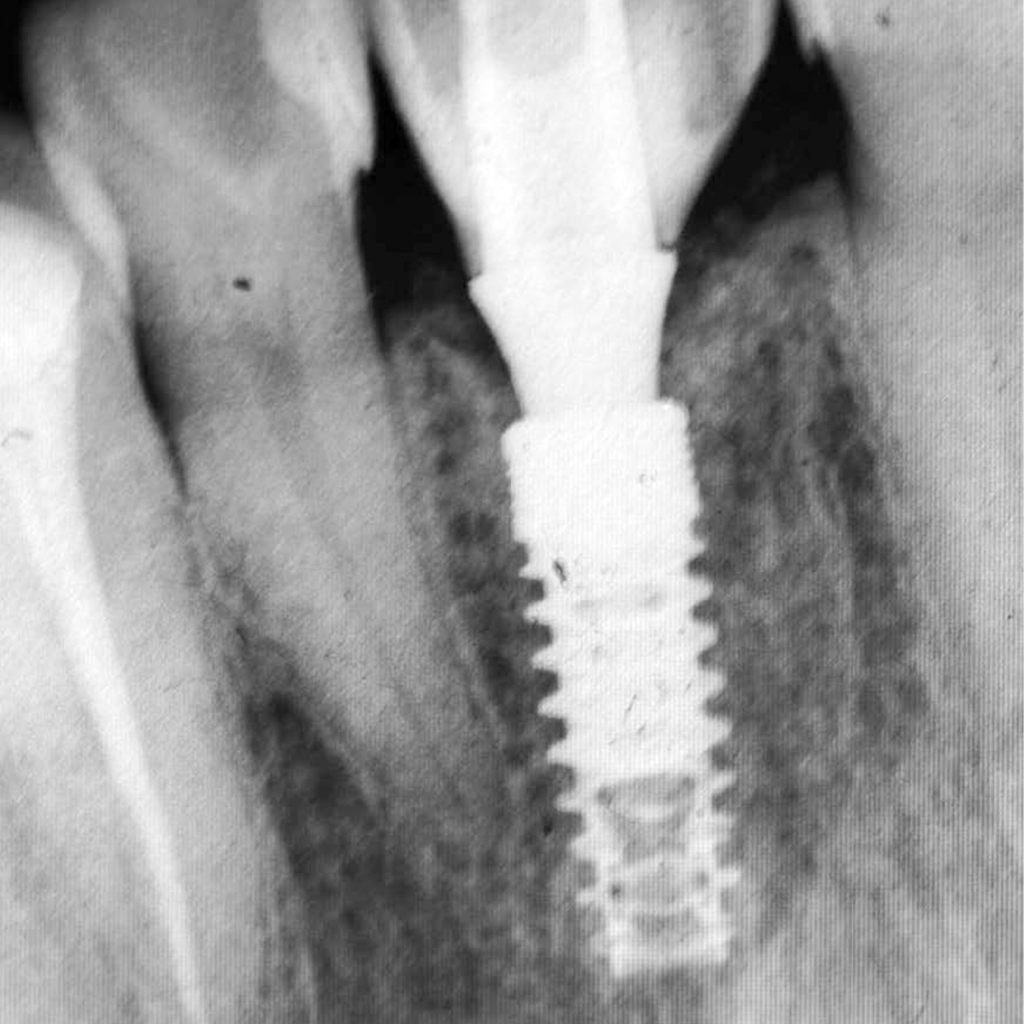

Desde 1985 tenho colaborado com o professor Per-Ingvar Brånemark e nos últimos anos, desenvolvi, juntamente com ele e Christian Brånemark, uma nova macro geometria do ápice do implante. Está parte apical do implante tem a função de reduzir o atrito, devido a seu corte preciso, controlando o torque de inserção, coletando lascas de tecido ósseo para o interior da câmara apical.

Since 1985 I have been collaborating with professor Per-Ingvar Brånemark and during the last years, I have, together with him and Christian Brånemark, developed a new implant tip.This part of the implant is reducing friction, due to precise cutting, reducing insertion torque and collecting bone chips inside the tip part of